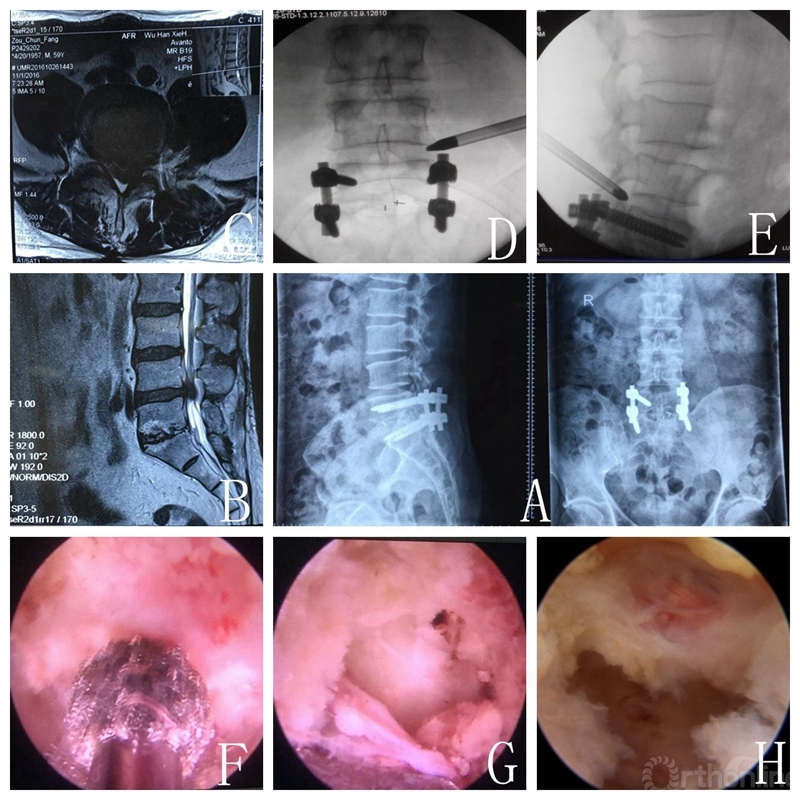

典型病例一:患者男性,59岁,因腰疼伴左下肢疼痛2月余入院。患者既往于2013年7月因L5S1LDH行椎间盘切除+植骨融合内固定术。

A.术前正侧位X线;B-C.术前MRI示L4/5LDH;D-E.术中X线透视下正侧位定位;F-H.孔镜下减压,摘除髓核。